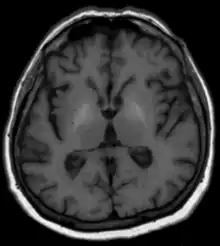

Les méthodes habituelles telles qu'analyses de sang, échographie et autres procédures d'imagerie par tomographie ainsi que la clinique[1] et, si nécessaire, une biopsie du foie avec examen histologique, sont disponibles pour diagnostiquer la maladie hépatique sous-jacente. En ce qui concerne la dégénérescence du cerveau, aucun changement n'est généralement visible sur la tomodensitométrie. L'IRM montre généralement une augmentation du signal dans les noyaux gris centraux sur les séquences natives pondérées en T1[1]. On soupçonne que la cause en est des dépôts de minéraux paramagnétiques, potentiellement réversibles après une transplantation hépatique[1],[2]. Les images pondérées T2 ne montrent généralement aucune anomalie. En termes de diagnostic différentiel, les changements de signal décrits ci-dessus sont parfois observés avec une nutrition parentérale à long terme mais également avec des calcifications idiopathiques. La maladie de Wilson doit également être prise en compte dans le diagnostic différentiel[1].